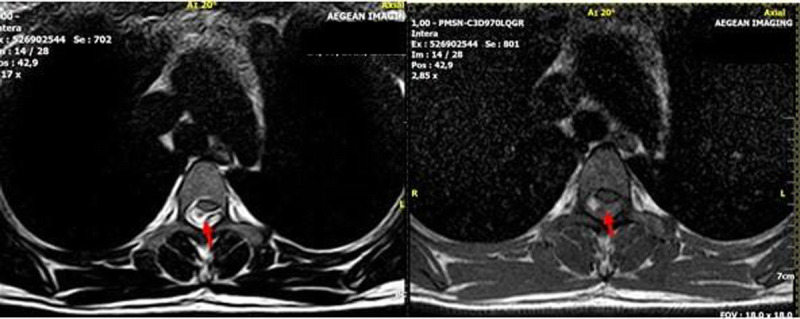

自发性脊髓硬膜外血肿(SSEH)是罕见的,特别是在怀孕期间。然而,SSEH是一种严重的紧急情况,必须立即处理,以防止母亲的永久性神经缺陷和死产。SEEH的病因和发病机制尚不清楚,尽管文献中描述了多种理论和诱发因素。在这个报告中,我们描述了一个怀孕的女性谁发展SSEH的情况。患者提供书面和知情同意发表她的临床信息和相关图像。在这里,我们报告了一例24岁的女性,孕龄31周,已知因子S缺乏和狼疮抗凝剂阳性,正在接受低分子肝素(LMWH)治疗。这种治疗有可能导致出血。此外,患者报告有10天的背部、乳房和下肢麻木和疼痛史。无外伤史报道。患者表现为急性(12小时)截瘫,立即在当地医院进行了磁共振成像(MRI)扫描,发现T1-T3位背侧硬膜外间隙急性出血(图1,2)。给予皮质类固醇,并通过直升机将患者转移到我们的急诊科,神经学评估显示双下肢力量受损(右:3/5,左:1/5),以及轻触丧失。心脏摄影和腹部超声显示心动过缓,脉搏中位数约为每分钟98次